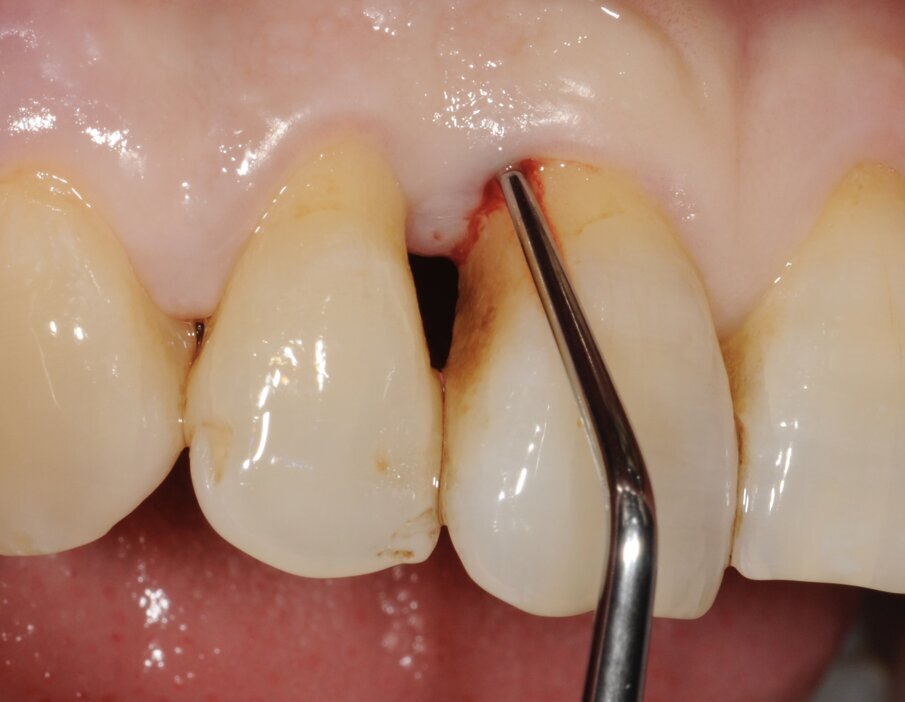

Un paziente di 56 anni non fumatore viene riferito alla nostra osservazione per il trattamento della parodontite. Dopo aver effettuato la diagnosi (parodontite generalizzata Stadio III, Grado C) il paziente è sottoposto a due sedute di scaling sopra gengivale (step 1) e successivamente a 4 sedute di debridement sotto gengivale effettuato con strumenti ultrasonici e manuali (step 2). Al momento della rivalutazione si registra un miglioramento degli indici di placca e di sanguinamento (FMPS e FMBS ≤ 20%) e una riduzione di tutte le tasche parodontali (PD<4 mm) in ciascun sestante a eccezione del secondo sestante. In questa regione si registra una tasca residua con PD = 6 mm a carico dell’elemento 1.1, associata a un riassorbimento osseo radiografico prevalentemente orizzontale (Figg. 1, 2). Considerando il miglioramento di tutti i parametri e degli indici parodontali e la presenza di una tasca con PD = 6 mm a carico di un solo elemento dentario si decide di ritrattare l’elemento 1.1 con terapia non chirurgica (step 3). La nuova ristrumentazione è stata effettuata seguendo il protocollo Clean&Seal che prevede l’associazione di ipoclorito di sodio stabilizzato con amminoacidi e acido ialuronico reticolato ad alto peso molecolare in combinazione con il debridement sotto gengivale. Dopo anestesia locale, è stato applicato all’interno della tasca l’ipoclorito di sodio stabilizzato con amminoacidi e lasciato agire per circa 60 secondi (Fig. 3). Successivamente è stata effettuata la strumentazione sotto gengivale mediante l’utilizzo di strumenti ultrasonici e manuali (Figg. 4, 5). Alla fine della procedura di strumentazione, nella tasca è stata effettuata un’irrigazione con soluzione salina sterile e la procedura di applicazione di ipoclorito di sodio e di strumentazione meccanica è stata ripetuta per 4 volte. Un fattore critico per garantire un risultato migliore è di evitare di instillare qualsiasi soluzione a base di clorexidina nella tasca, in quanto inibisce l’adesione cellulare. Alla fine del trattamento meccanico è stato inserito l’acido ialuronico reticolato ad alto peso molecolare all’interno della tasca per stabilizzare il coagulo e accelerare la guarigione (Fig. 6). Il controllo clinico è stato effettuato dopo 6 settimane dal trattamento con completa chiusura della tasca (Fig. 7).